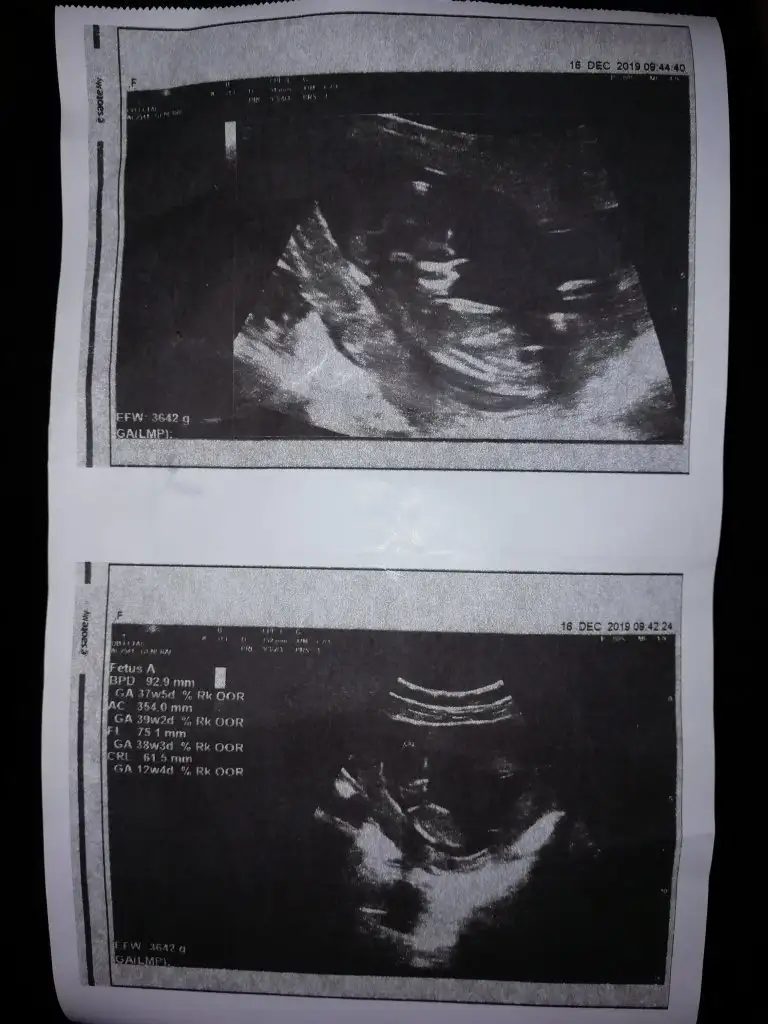

Buda bizim Nub umuz bı tahminde bulunur musunuz ☺️ bıraz karanlık cıktık ama olabıldiği kadar. Dr erkek dedı ilerleyen zamanda netlestırrız dedı. Sızcede oylemı tesekkürler .

• IMG_20191216_112522.webp

IMG_20191216_112522.webp

42,7 KB · Görüntüleme: 76